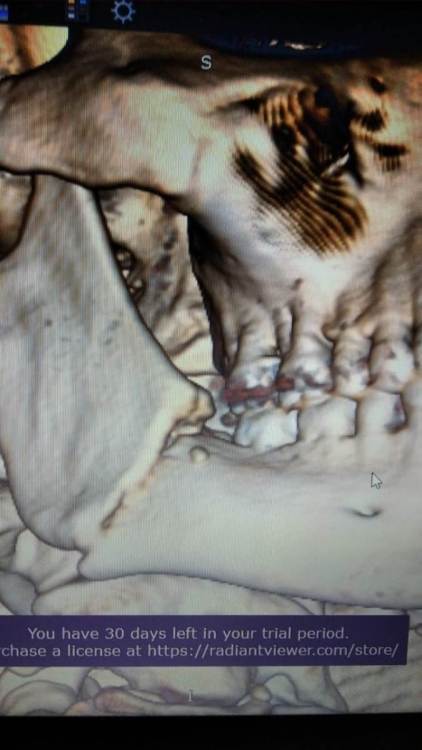

Russ Опубликовано 16 августа, 2022 Поделиться Опубликовано 16 августа, 2022 Доброго времени суток, Уважаемые специалисты и посетители форума. Очень нужна Ваша помощь. 6 недель назад получил закрытый перелом челюсти справа со смещением. Зуб мудрости удалили, зашинировали, ожидании операции провел неделю в стационаре , но был выписан, сказали "так сростется". Загрузил фото рентгена (10 дней после наложения шин) и фото КТ (6 недель). Бежать заново ломать, пока не схватилось до конца все? Заранее спасибо. Ссылка на комментарий

kramer Опубликовано 17 августа, 2022 Поделиться Опубликовано 17 августа, 2022 Отломки явно не на своем месте. Надо делать остеосинтез. 1 1 2 Ссылка на комментарий

Irouil Опубликовано 19 августа, 2022 Поделиться Опубликовано 19 августа, 2022 7 часов назад, Russ сказал: @Irouil @Doc Я прошу прощения, я правильно понимаю, что чувство сжатия (тесноты) у зубов со стороны перелома возникло из-за того, что неправильно сросшиеся отломки сдавливают нижнечелюстной нерв с этой стороны? Спасибо. Нет, скорее всего зубы просто не в прикусе Главный показатель функциональной реабилитации после перелома нижней челюсти - прикус. Если кусается жуется как обычно, то в небольших смещениях нет ничего криминального. Но если "зубы жмут", как я это понимаю, это может быть признаком нарушения прикуса. Последствия, как верно выше писал @Doc, в отдаленной перспективе не очень приятные - сустав,зубы, связочный аппарат перегружены. 1 1 Ссылка на комментарий